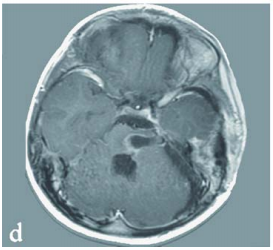

由巴教授主刀完成病灶全切手术,术中应用体感诱发电位及脑干听觉诱发电位监测,结合神经导航技术实现精准切除。术后十日MRI证实病灶完全切除,脑干受压解除,第四脑室形态恢复正常。患儿神经功能持续改善,后续接受系统化神经康复治疗。